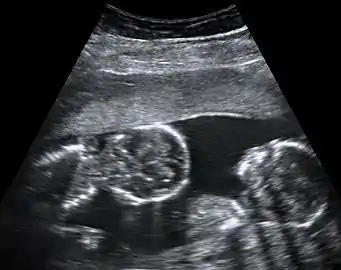

Dichorionic-diamniotic twins at 8 weeks and 5 days since co-incubation as part of IVF. The twin at left in the image is shown in the sagittal plane with the head pointing towards upper left. The twin at right in the image is shown in the coronal plane with the head pointing rightwards.

Abdominal ultrasonography of monoamniotic twins at a gestational age of 15 weeks. There is no sign of any membrane between the fetuses. A coronal plane is shown of the twin at left, and a sagittal plane of parts of the upper thorax and head is shown of the twin at right.